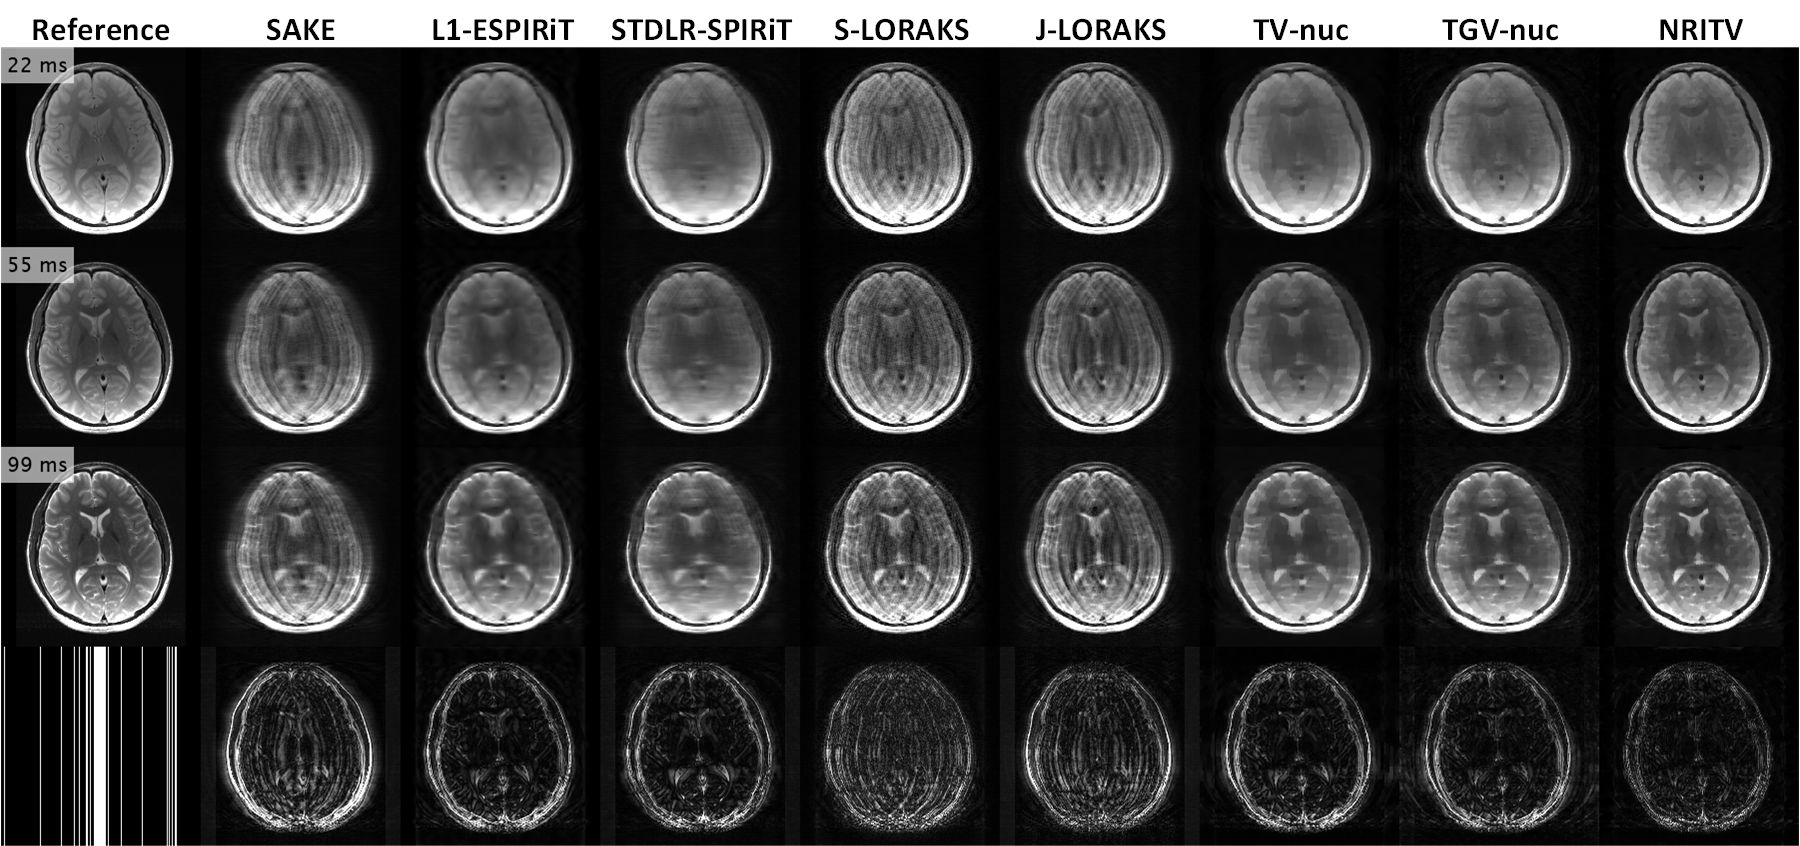

Figure 6: Magnified views of the results for the brain data at R=7𝑅7R=7 and σ=0.02𝜎0.02\sigma=0.02. Some errors in the competing methods and their corrections with the proposed one are marked. Appendix Fig. 12 shows full size FOV’s, error maps and the sampling pattern for this experiment.

Fig. 6 shows reconstructions for a triple-contrast in-vivo brain dataset from [14] graciously provided by Dr. Chatnuntawech. The data had been collected from a healthy volunteer with Institutional Review Board approval and informed consent at 3T (MAGNETOM Trio, A Tim System, Siemens, Erlangen, Germany) using a turbo spin-echo (TSE) sequence with the important parameters: FOV = 22×22 cm22222superscript cm222\times 22\text{ cm}^{2}, voxel size = 0.9×0.9×3 mm30.90.93superscript mm30.9\times 0.9\times 3\text{ mm}^{3}, repetition time (TR) = 444 s and echo times (TE) = 22,55,9922559922,55,99 ms with 32 receive coils. However, for speed, ESPIRiT’s coil compression was used to reduce this number to 8. White Gaussian noise with standard deviation σ=0.02𝜎0.02\sigma=0.02 was added, then k-space was retrospectively undersampled at R=7𝑅7R=7. Fig. 6 shows that SAKE and the LORAKS-based solutions have failed to denoise and de-alias the data. STDLR-SPIRiT, L1-ESPIRiT, TV-nuc and TGV-nuc output over-smoothed solutions (e.g. blue arrows in the 222222- and 999999-ms contrasts pointing to the temporal horns and white matter, yellow boxes encompassing the straight sinus in the 222222- and 999999-ms contrasts). Loss of contrast at skull is observed with the same methods (yellow boxes in the 555555-ms contrast). NRITV resolves all these drawbacks and finds the best balance between noise removal and detail retention. Full-size views for all methods along with error maps and sampling pattern can be observed in Fig. 12. Selected parameters for the competing methods are given in Table 5. NRITV used λ=3×103𝜆3superscript103\lambda=3\times 10^{-3} and ESPIRiT-based maps with 22%percent2222\% error.